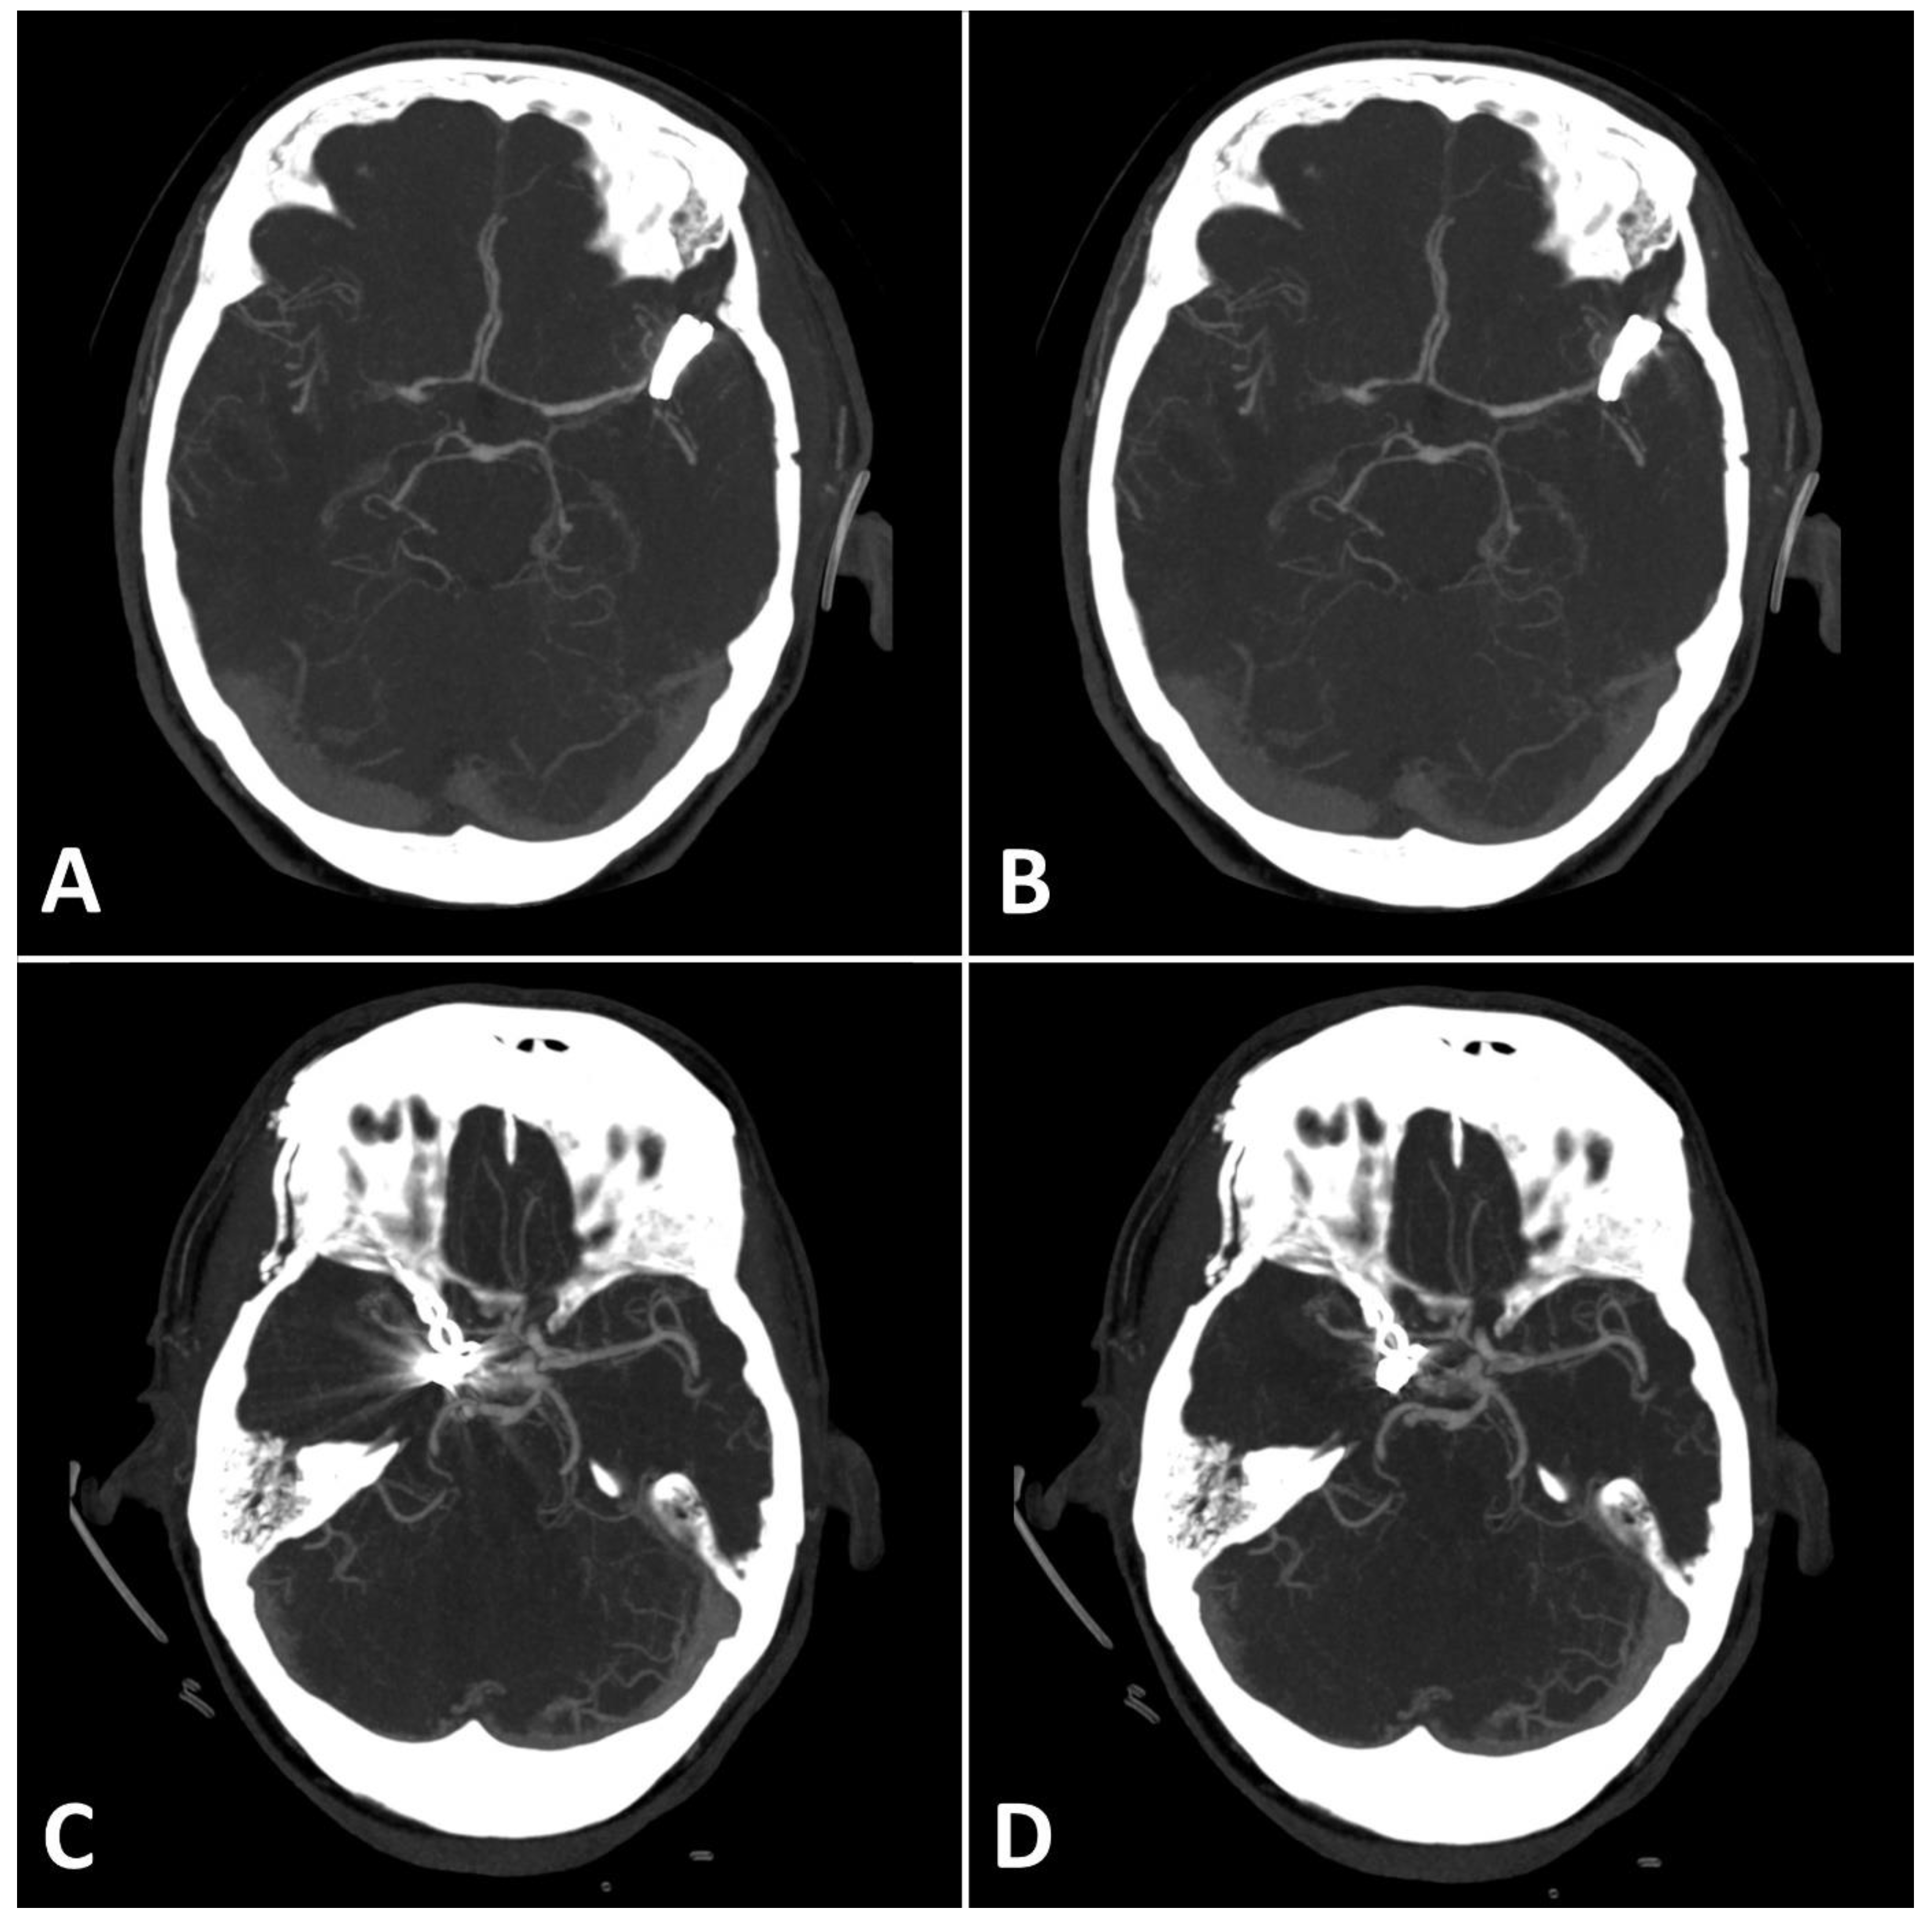

Metal artifact index (MAI) (which was considered to be the mean image noise) was significantly reduced in SEMAR images compared to standard images in close vicinity to (70.9 ± 22.1 vs. 331.8 ± 157.5, respectively) and more distant from the coil package (24.7 ± 6.7 vs. 52.4 ± 20.3, respectively; p < 0.001 each). Figure 2 and Figure 3 demonstrate significantly improved image quality and visualization of arteries after applying the SEMAR algorithm on images with coil-artifacts.

Figure 2.

Exemplary follow up UHR-CT-angiography in axial (A,B) and sagittal (C,D) plane without (A,C) and with SEMAR (B,D) of a 56-year-old female after intracranial coil-embolization of a left sided posterior communicating artery aneurysm. All images were reconstructed as MIP (Maximum Intensity Projection) with 12.5 mm slice thickness. SEMAR significantly improves image quality, even in vessels directly adjacent to the coil package like the anterior communicating artery (white arrow in (B)), the contralateral terminal carotid artery (arrowhead in (B)), the anterior cerebral artery (white arrow in (D)), and the posterior communicating artery (arrowhead in (D)).